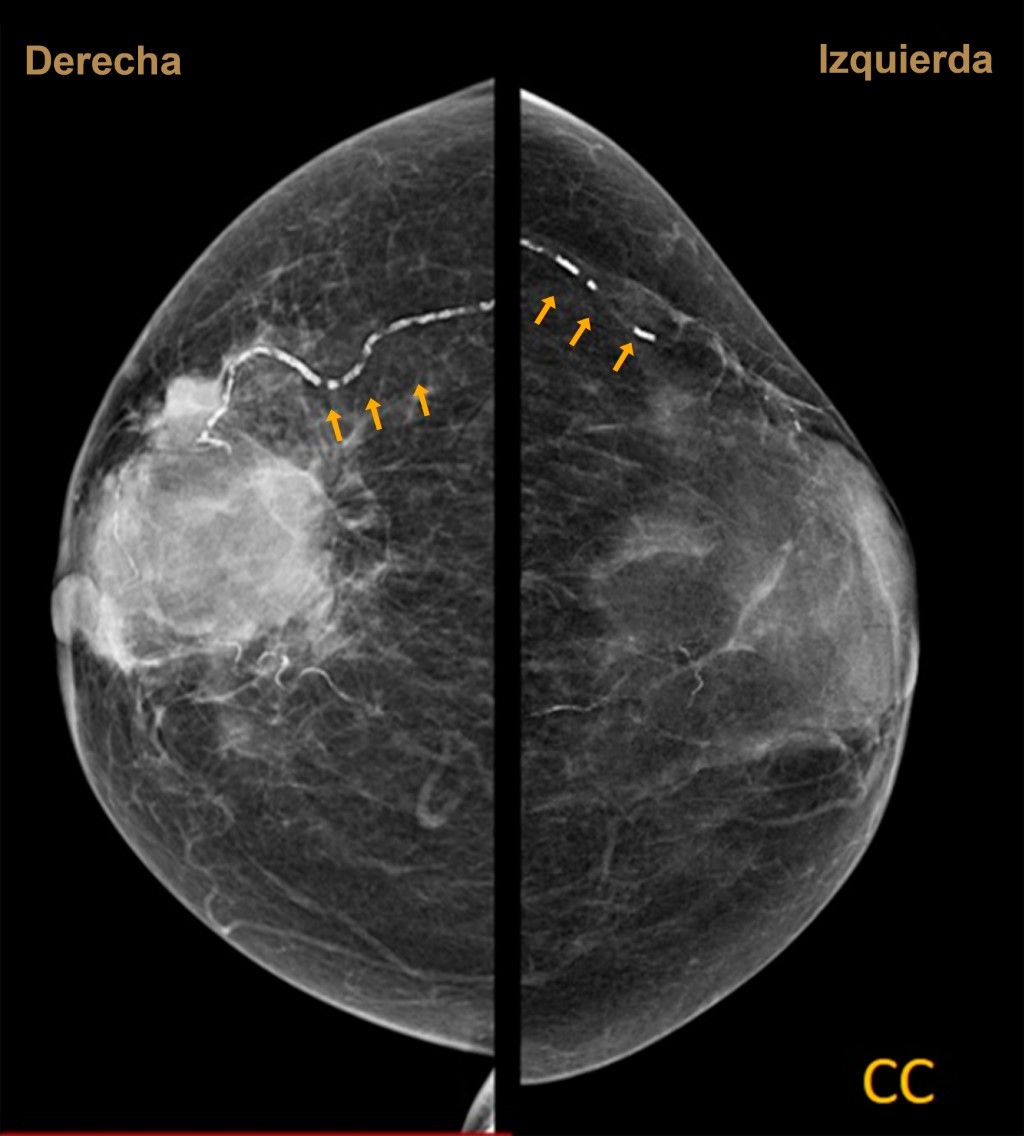

En la mastografía, estas calcificaciones suelen ser lineales y paralelas, en un patrón que se denomina "vía de ferrocarril", ya sean en forma focal o difusa.

Se trata de paciente femenino de 74 años con antecedente de diabetes mellitus tipo 2. Acude a mastografía de tamizaje. Se aprecian dos proyecciones, densidad mamaria tipo B, con un nódulo irregular hiperdenso de márgenes espiculados de 5.1 × 5.2 cm en sus ejes mayores y se aprecian calcificaciones lineales (Figuras 1 y 2). Se otorga categoría BI-RADS 5.

Figura 2